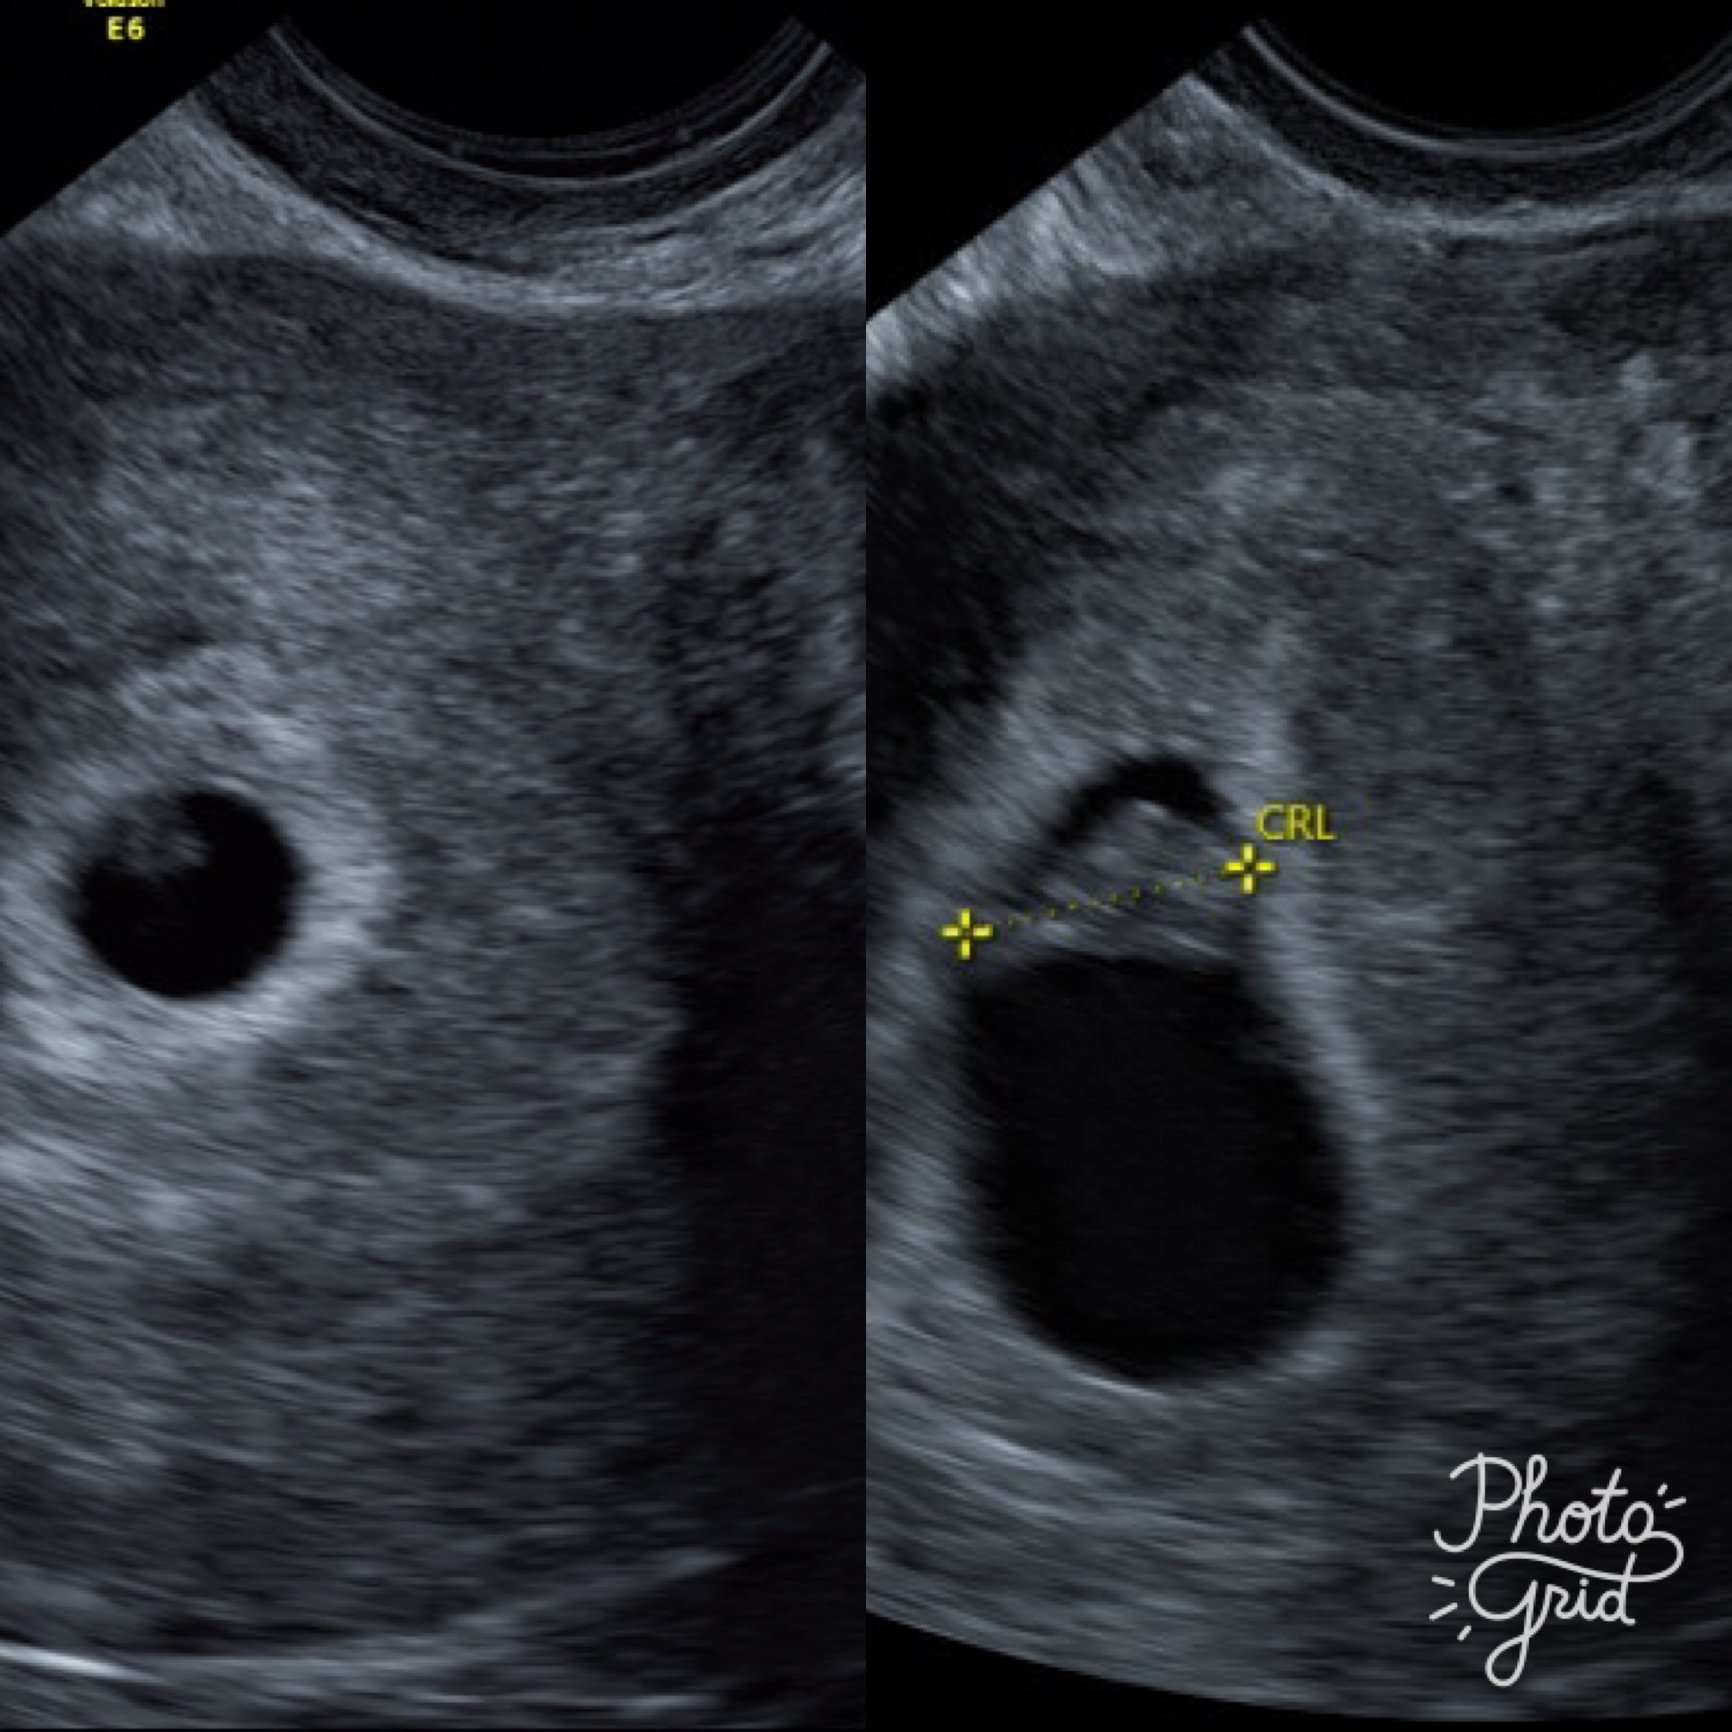

I had my third U/S on Friday. I was exactly 9 weeks. Baby measured right on track for 1/5 due date and had a heart rate of 182. My doctor was super pumped! You can even see baby's little arms and legs. Legs are to the left, head is to the right, little belly in the middle, and then a little arm sticking up. So cute!

Baby at 9 weeks. Measuring right on track and a healthy heartbeat. Baby was wiggly during the ultrasound.